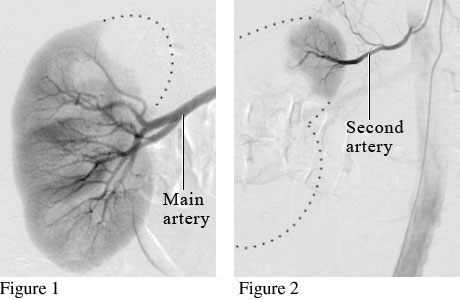

Many people have more than one artery for blood flow to the kidneys. Figure 1 is an angiogram showing the main artery supplying blood flow to the kidney. Figure 2 is an angiogram showing a second artery helping to supply blood to the kidney.